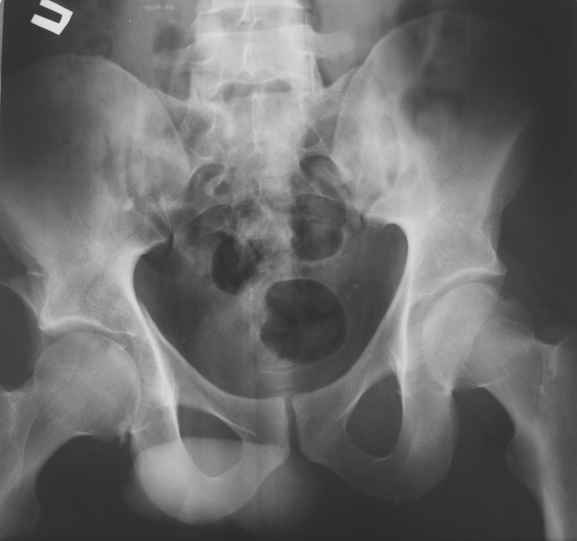

Уважаемые коллеги! Прошу посоветовать как лечить больного с двусторонним повреждением тазобедренных суставов. Пациент 30 лет поступил к нам в клинику по поводу закратого поперечного перелома свода, перелома задне -вехнего края правой вертлужной впадины, подвздошного вывиха правого бедра. Постравматического неврита правого седалищного нерва. Закрытого запирательного вывиха левого бедра. травма автодорожная 3 недели назад. Вправление вивихов при поступлении по месту жительства, получал скелетное вытяжение (слева в течении 2 недель).На контрольной Р-грамме обнаружена импрессия верхнего полюса головки левого бедра. Выполнено КТ.Планируем выполнить остеосинтез перелома правой ВВ наружным доступом.Подскажите пожалуйста, необходимо что либо предпринимать по поводу перелома головки левого бедра (в "Мюллере" описана костная пластика дефекта)? И как рано можно разрешить нагрузку на левую ногу.